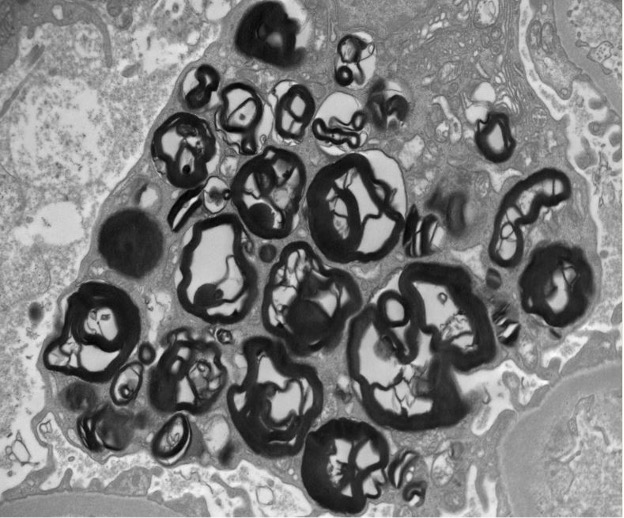

Figure 3 (Electron microscopy Photo) Segmental podocytes contain numerous rounded electron-dense lipid inclusions (myelin figures, aka zebra bodies)

Kidney biopsy pathologic findings by light microscopy (LM) and electron microscopy (EM) are quite characteristic in Fabry disease. LM shows visceral glomerular epithelial cells (podocytes) and distal tubular epithelial cells with expanded cytoplasm and a marked foamy appearance (vacuolization), most prominent on the trichrome stain and seem as blue inclusions on toluidine blue stained plastic embedded LM of the EM specimen10. EM reveals podocytes that have prominent and expanded cytoplasm that contains numerous rounded electron-dense lipid inclusions (myelin figures, aka zebra bodies). Myelin figures or zebra bodies represent deposits of Gb3 primarily within enlarged secondary lysosomes as lamellated membrane structures11. These inclusions, composed of concentric layers with a periodicity of 3.5 to 5 nm and often an onion skin appearance, are considered a hallmark of glycolipid storage disorders12. These lipid inclusions may be seen in all glomerular cell types (most prominently podocytes), arteriolar smooth muscle cells, and tubular cells (mostly distal tubules) 11. Podocyte foot process effacement may range from focal to diffuse. Immunofluorescence staining does not typically contribute to the diagnosis but may be useful in excluding other coincident kidney disorders.

The ultrastructural findings of Fabry disease on kidney biopsy are highly characteristic and diagnostic. However, similar inclusions have been described in drug/medication-induced phospholipidosis secondary to quinine containing medications (chloroquine, hydroxychloroquine, anti-malarial agents), amiodarone, mercuric chloride, cisplatin, silicon, cadmium, and possibly other medications 13. The location of the inclusions is sometimes helpful in making the distinction between these diseases. Lamellar inclusions associated with gentamicin occur in proximal tubules, whereas in Fabry disease, the inclusions are most striking in podocytes and distal tubules 14.